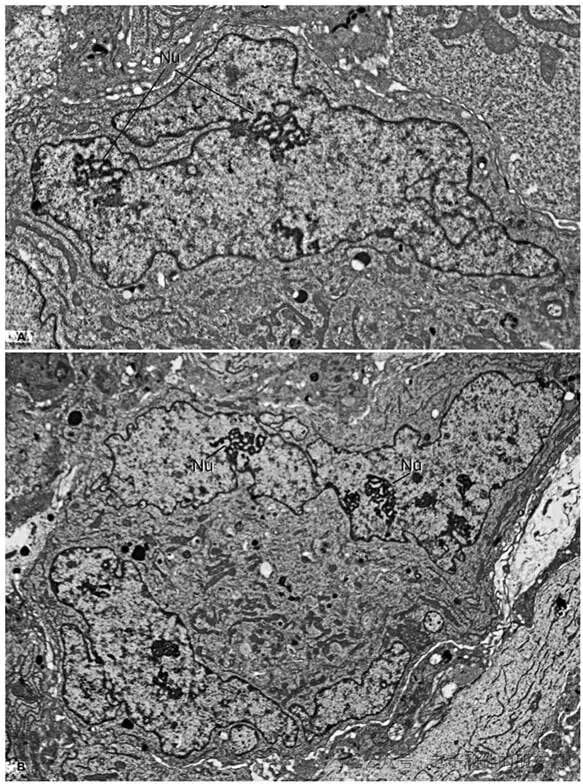

用电子显微镜放大后,放大1000倍甚至更多,能清楚看到恶性癌细胞的细胞核。其中一幅放大 1000 倍的图像中(对应图A),肿瘤细胞的核特别大,直径能超过 20 微米,比正常细胞核大不少,形状是分叶状,里面含有增大的核仁,核仁内还能看到特殊的核仁网,而且因为核体积太大,核质比也失去了平衡,核凹陷和折叠在多种癌症中都能见到,但这种分叶现象相对少见。

放大倍数:图 A ×1,000;图 B ×800

另一幅放大 800 倍的图像(对应图 B)展示的是同一恶性肿瘤中的另一个细胞,呈双核状态,也就是一个细胞里有两个核,它的核同样很大,直径超过 30 微米,也是分叶状,里面含有多个增大的核仁,核仁内同样能看到核仁网。和癌细胞核的常见特征一样,这里的浓缩染色质也就是异染色质分布得乱七八糟,还会有一堆堆密集的异染色质聚集体。